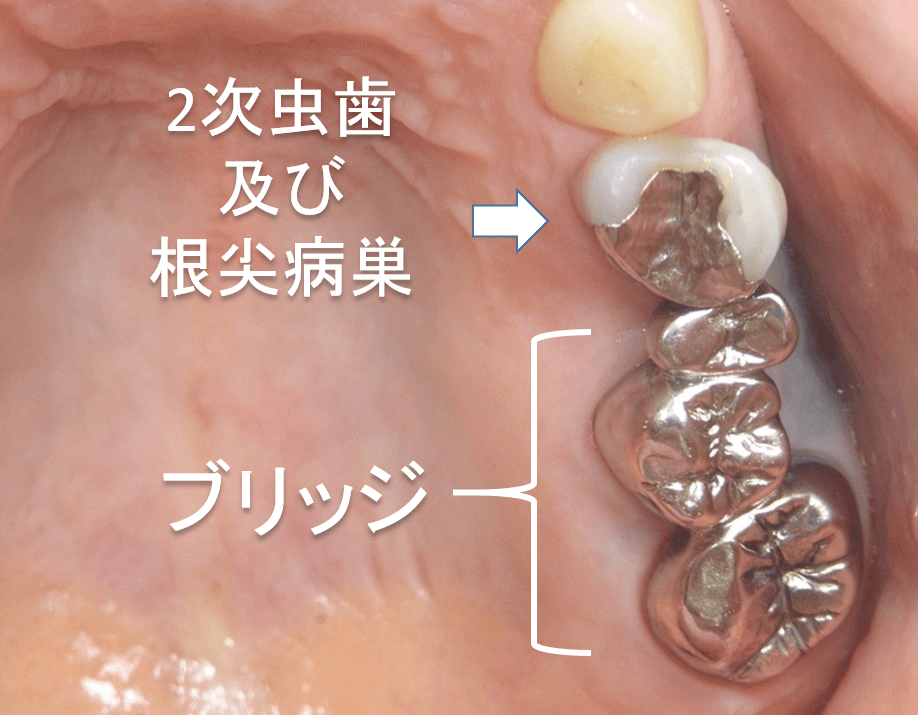

インプラント治療で回復したケース

こんにちは。 南館歯科クリニックの院長の木村です。 左下臼歯部(奥歯)の欠損部をインプラント治療で回復した50代の女性のケースをご紹介します。 治療前の状態。 左下奥歯には、延長ブリッジ…

綺麗になりました。

こんにちは。 南館歯科クリニックの院長の木村です。 右上の臼歯部の治療ケースをご紹介します。 治療前の状態⇩ ブリッジの土台になっている歯は、3年くらい前に、悪なってしまった歯根だけを抜…